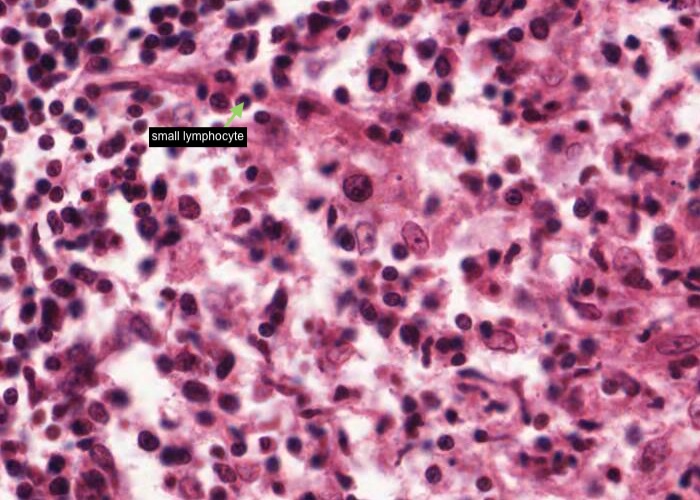

This tonsil has many plasma cells. A good place to look for them is right under the epithelium. Make a point of looking at a number of examples until you can recognize them by their cartwheel nucleus, their basophilic cytoplasm (far more extensive than small lymphocytes have) and possibly by their pale-stained Golgi body next to the nucleus.

The spaces between collagen fibres of the capsule happen to be other favorable places to look because plasma cells here can be seen without bunches of other cells on top of them.